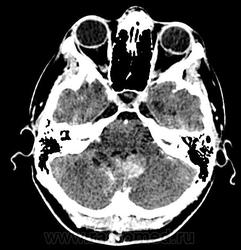

Девушка 30 лет. Поступила с диагнозом Эпилепсия. Неоднократные синкопы, начавшиеся после родов. Роды в начале марта, все благополучно. После родов, как-то так плохо все,шатает, голова болит. Через месяц обратилась в республиканскую больницу, выполнена кт- смешання гидроцефалия. Пролечили и выписали с диагнозом Дистония. Как-то так.

-признаки интравентрикулярной окклюзи выходных отверстий 4 желудочка, с резким расширением всех отдела желудочковой системы.

-резкое сужение охватвающей и большой цистерн

-выраженное расширение хиазмальной и предпонтийной цистерн

-межполушарная,латеральные щели и субарахноидальные пространства значительно уменьшены в объеме за счет увелиения желудочков и отека мозга

-истонены кости основания черепа,усилен рельеф внутренних костных пластин,углублено и расширено турецкое седло,опускание СЧЯ

-ствол и продолговатый мозг в дорсальном отделе уплощены,смещены вентрально

-в полости 4 желудочка объемное образование с учсатками кровоизлияния, с распространением каудально, признаки вклинения миндалин в БЗО,большая цистерна и САП кранио-вертебрального перехода не прослеживаются.

и добавлю,что это было за месяц до "нашей с ней встречи",тогда на кт в респусликанской б-це... кровушка лишь добавилась...